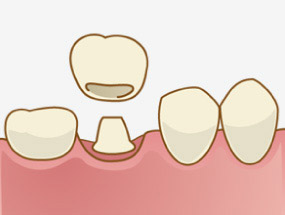

クラウンは、虫歯を削った後に被せる人工の歯のことで、「差し歯」や「被せ物」と言われています。比較的小さな虫歯の場合はインレー(詰め物)による治療を行いますが、大きな虫歯や根管治療(神経を取る)をした後は、詰め物ではなくクラウン(被せ物)による治療となります。

コアとは、クラウン(被せ物)を被せるための土台に当たります。この部分が歯の中に差し込まれるカタチになるので「差し歯」の由来となっています。

神経を失った歯は脆くなってしまうので、コアと呼ばれる土台を差し込み、補強した上で、被せ物をします。また、神経がなくなると、神経が通っていた部分は空洞になるため、また細菌感染が起こらないよう、樹脂とコアで密閉することで、二次感染を防ぐという効果も担っています。